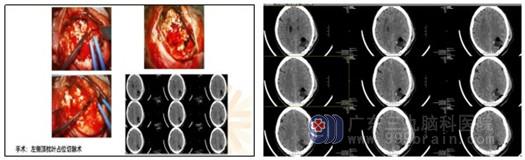

(术后CT)

术后,林叔叔在家人的陪伴照顾、医护人员制定的康复治疗下,身体与心理上都逐渐好了起来,他脸上又露出了许久不见的笑容!目前林叔叔正在进一步恢复中,后续还需进行放化疗等相关治疗。